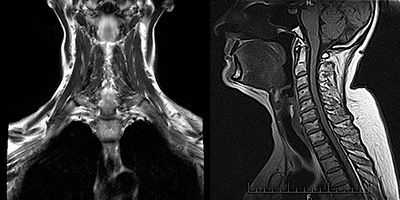

2. Термин радикулопатии объединяет различные симптомы и признаки, возникающие в результате преходящего или стойкого повреждения нерва при его выходе из спинного мозга на уровне межпозвоночных отверстий. Результаты исследований проводимости обычно в норме. ЭМГ выявляет признаки неврогенных изменений (например, фибрилляции и изменения ПДЕ) в мышцах, иннервируемых определенным корешком, тогда как мышцы, иннервируемые не вовлеченными в патологический процесс корешками, интактны. Характер неврологических изменений зависит от степени тяжести процесса, длительности заболевания и степени восстановления (реиннервации).

- ЭМГ используется для подтверждения повреждения корешка и определения уровня поражения. Следует заметить, что патологические изменения по результатам ЭМГ наблюдались лишь примерно у 90 % пациентов с шейной или пояснично-крестцовой радикулопатиями, обнаруженных при оперативном вмешательстве. Таким образом, нормальные результаты ЭМГ не исключают наличия радикулопатии.